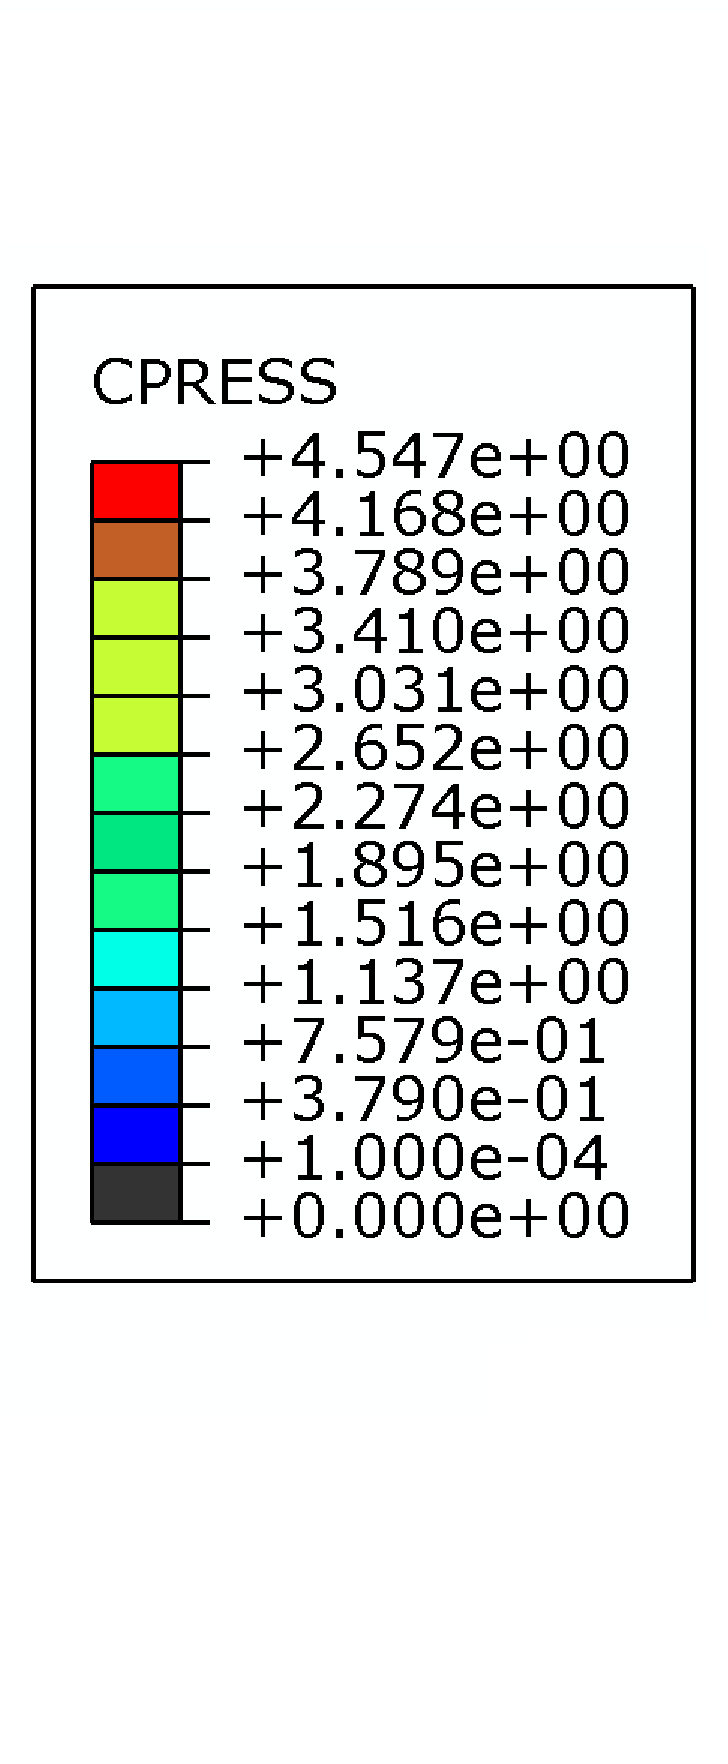

The bottom surface of the tibia head is fixed, and two translational DOFs in the horizontal plane of the top surface of the femur head are also constrained. On the top surface of the femur head, a vertical load of up to [72] is applied to induce contact in the knee joint. The displacement contours () from different views are shown in Fig. 32. It is obvious that the deformation occurs mainly in the meniscus. The femur, tibia and articular cartilages are similar to rigid bodies. This phenomenon meets the expectation because the Young’s modulus of the meniscus is significantly smaller than those of the bones and articular cartilages. The meniscus is squeezed into the joint space and there is lateral extension of the meniscus. The large deformation of the meniscus increases the contact area which is helpful to reduce the contact pressure.

The contact pressure distributions () are depicted in Fig. 33. To illustrate the distribution clearly, contact pressure values smaller than are not included in the contour. It is obvious that the contact pressure on the articular cartilage has a similar distribution and magnitude compared to that on the meniscus. Besides, the contact pressure on the articular cartilage has a similar distribution from Ref. [72].

The development of the contact on the articular cartilage is recorded, as depicted in Fig. 34. Note that only the area where the contact pressure is greater than has been taken into account. Generally speaking, with increasing the vertical load , the contact area is increasing while its increasing rate is reducing. The average contact pressure increases during the loading history. Before the vertical load increases up to , the increasing rate of the average contact pressure is basically reducing. However, when the average contact pressure increases almost linearly because the contact area increases only slightly.